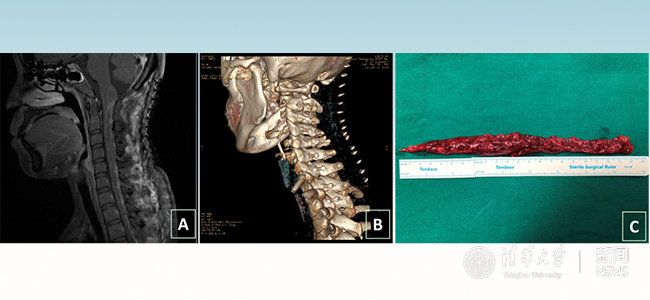

术后影像。图A示:肿瘤完整切除,图B示:椎板完整复位,图C示:肿瘤标本。

4个小时、6个小时、8个小时过去了,手术终于进行到了最重要的时刻:切除最后延髓的部分肿瘤。由于紧靠循环中枢,患者心率开始在50-100次/分波动,麻醉医生迅速调整药物,稳住患者心率、血压。最终肿瘤完整地切了下来,长度达到21厘米。21点30分,小甜手术成功结束,整个过程历时14个小时,她的母亲握着王贵怀的双手,双眼噙着泪花,不停地说着感谢的话。